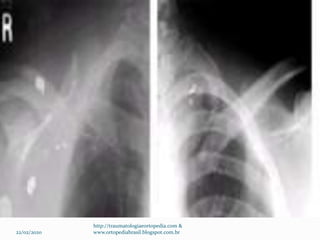

Exames Radiográficos

 Rx de clavícula AP

 Radiografia apical Oblíqua

 TC  Terço proximal – raro –

 Terço distal – Rx com estresse (4,5 Kg) para avaliação

dos ligamentos